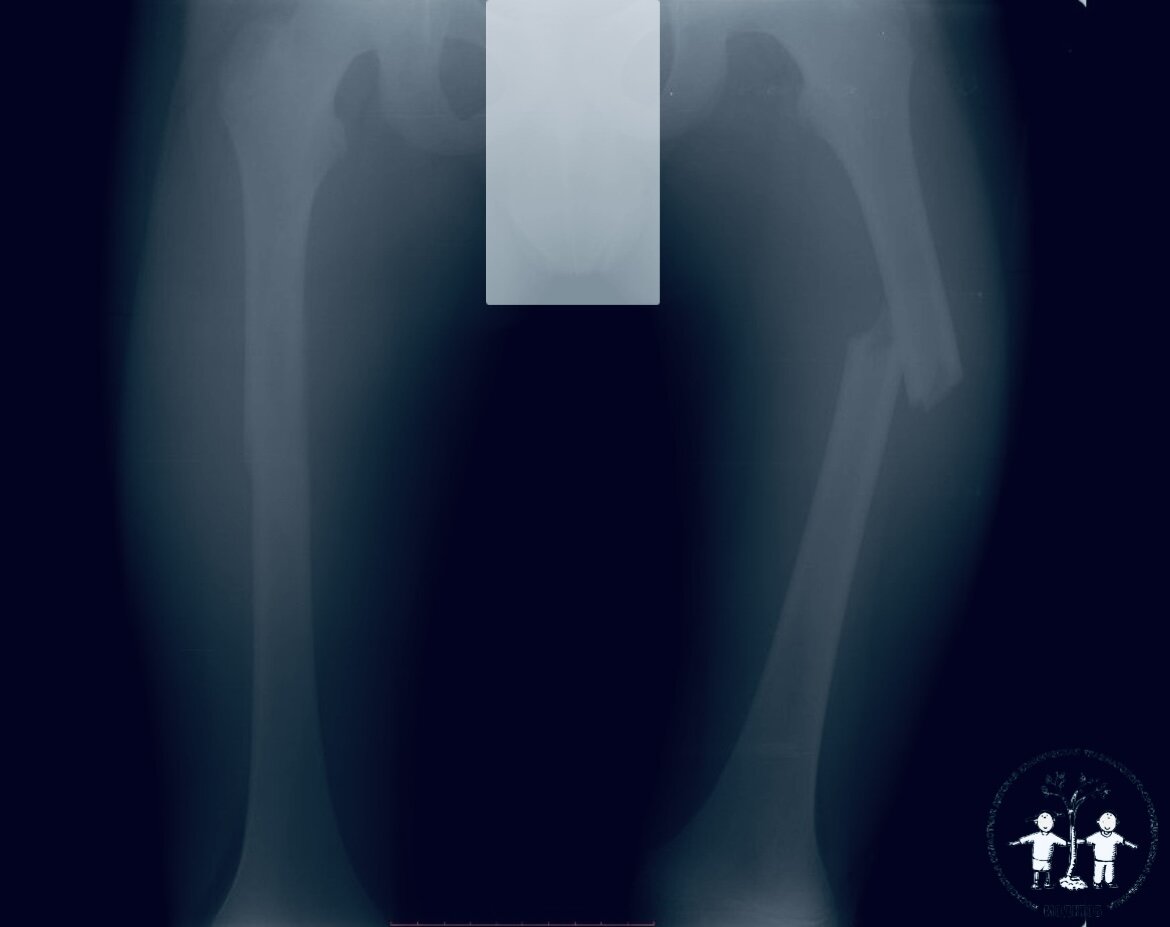

«Ребенок был доставлен в больницу бригадой скорой помощи. Пациент жаловался на болезненность при пальпации в области средней трети правого и левого бедра. Отмечалась деформация нижних конечностей. После всех диагностических мероприятий проведено хирургическое лечение – отломки костей сопоставлены и фиксированы титановыми эластичными стержнями (TEN)», - прокомментировал Григорьев Александр Владимирович, главный внештатный детский специалист травматолог-ортопед Минздрава Московской области, главный врач МОДКТОБ.